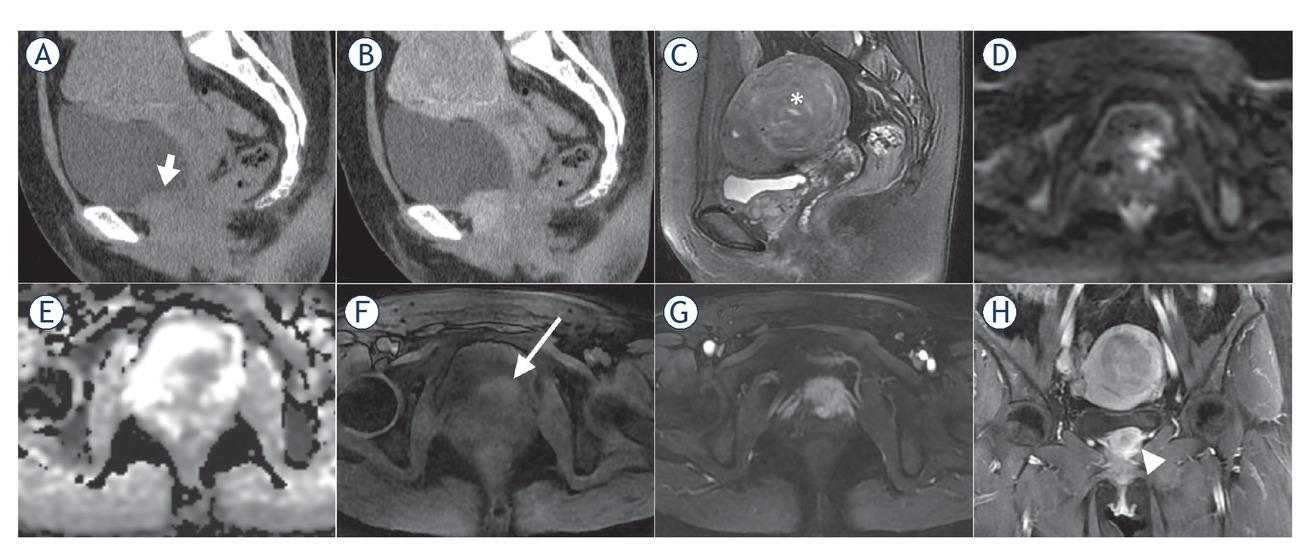

CT and MR image characteristics*

| Computerized tomography (n = 13) | |

|---|---|

| Density | Moderate or slightly lower density |

| Enhancement characteristics | Moderate to marked enhancement |

| Calcification | None |

| Cystic degeneration or necrosis | Rare (n = 2) |

| Haemorrhage | None |

| Magnetic resonance imaging (n = 8) | |

| T2-weighted imaging | Slight hyperintensity |

| Diffusion-weighted imaging | Hyperintensity |

| Apparent diffusion coefficient (ADC) map | Hypointensity (ADC value, 0.883±0.126×10-3 mm2/s)** |

| T1-weighted imaging | Slight hyperintensity |

| Enhancement characteristics | “Fast in and slow out” pattern |